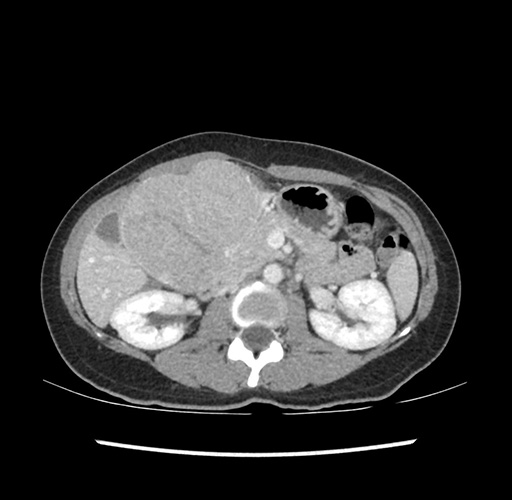

Imaging Analysis

Look through the patient's CT scan to identify any areas of concern for the necessary procedure.

Based on your CT findings, which issue(s) would give reason for "planned slowing down moment(s)" in this case?